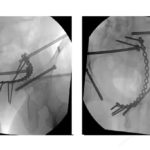

Posterior Pelvic Ring fixation

Courtesy: Prof Rommens, Germany and Egyptian pelvis and Hip Society